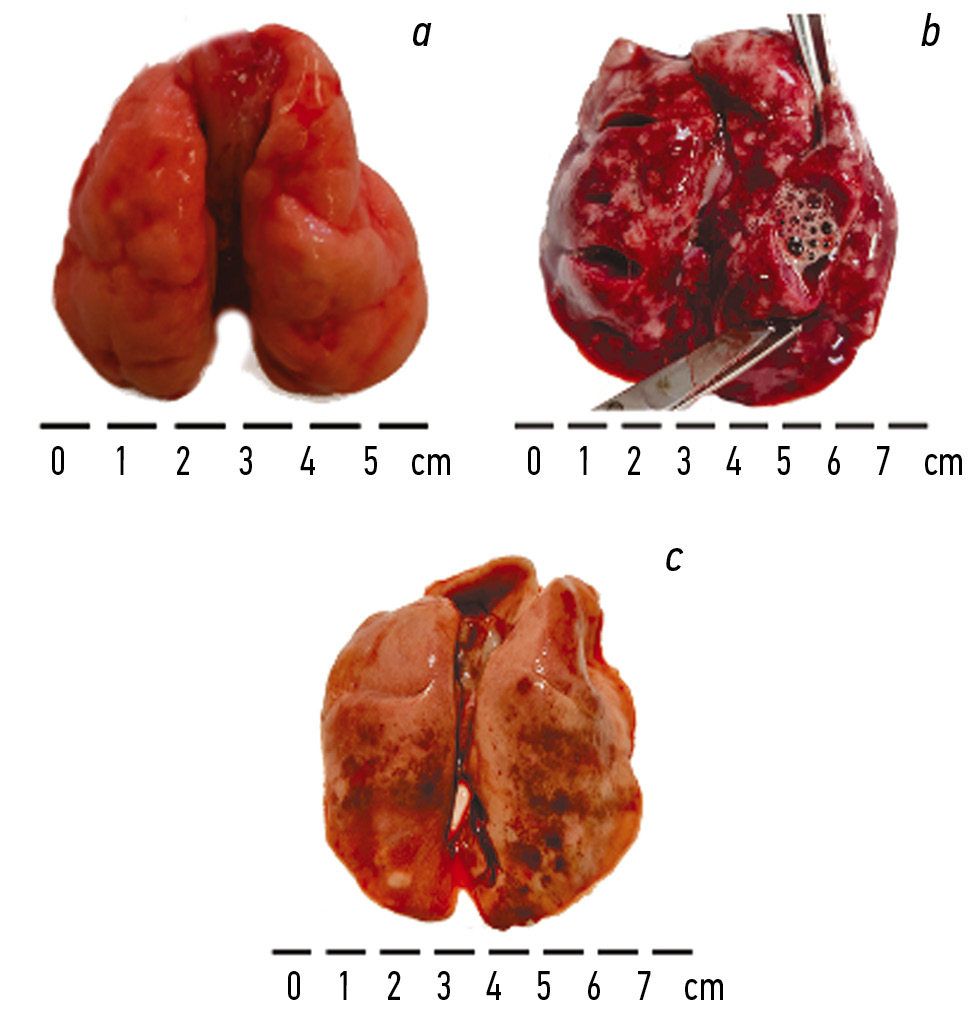

In rabbit 2, 13 hours after exposure, sharply increased motor activity, gurgling breathing, foamy discharge from the mouth and nose, and convulsions were observed, leading to death. Macroscopic examination revealed enlarged lungs with smoothed interlobar folds, lung surface hemorrhages, and foamy discharge from the trachea and at the incision (Fig. 3). The lung ventilation coefficient was 11.8 relative units. Histological examination revealed thinning of the interalveolar septa walls, homogeneous contents, and erythrocytes and neutrophils in the alveolar cavity (Fig. 4).

Fig. 3. Macropreparations of rabbit lungs obtained after exposure to the thermal destruction products of fluoroplastic-4 (1.5 HLC50). Rabbit 1 (a) and 3 (c) — lungs were obtained 7 days after exposure, rabbit 2 (b) — after death (13 hours after exposure)

Рис. 3. Макропрепараты легких кроликов, полученные после воздействия продуктов термодеструкции фторопласта-4 (1,5 HLC50). Кролик 1 (a) и 3 (c) — легкие получены на 7 сут после воздействия, кролик 2 (b) — после летального исхода (через 13 ч после воздействия)

The lungs of rabbit 1 (control) were pink, folds were visible between the lobes, and no foamy discharge was observed at the incision (Fig. 3). The lung ventilation coefficient was 5.6 relative units. Slides showed normal histoarchitecture of lung tissue (Fig. 4). The lungs of rabbit 3 were slightly enlarged and pinkish, with isolated hemorrhagic lesions on the surface; no foamy discharge from the trachea was seen at the incision (Fig. 3). The lung ventilation coefficient was 6.9 relative units. Microscopic examination showed moderate thickening of the interalveolar septa filled with erythrocytes, and the alveolar cavities were clear.